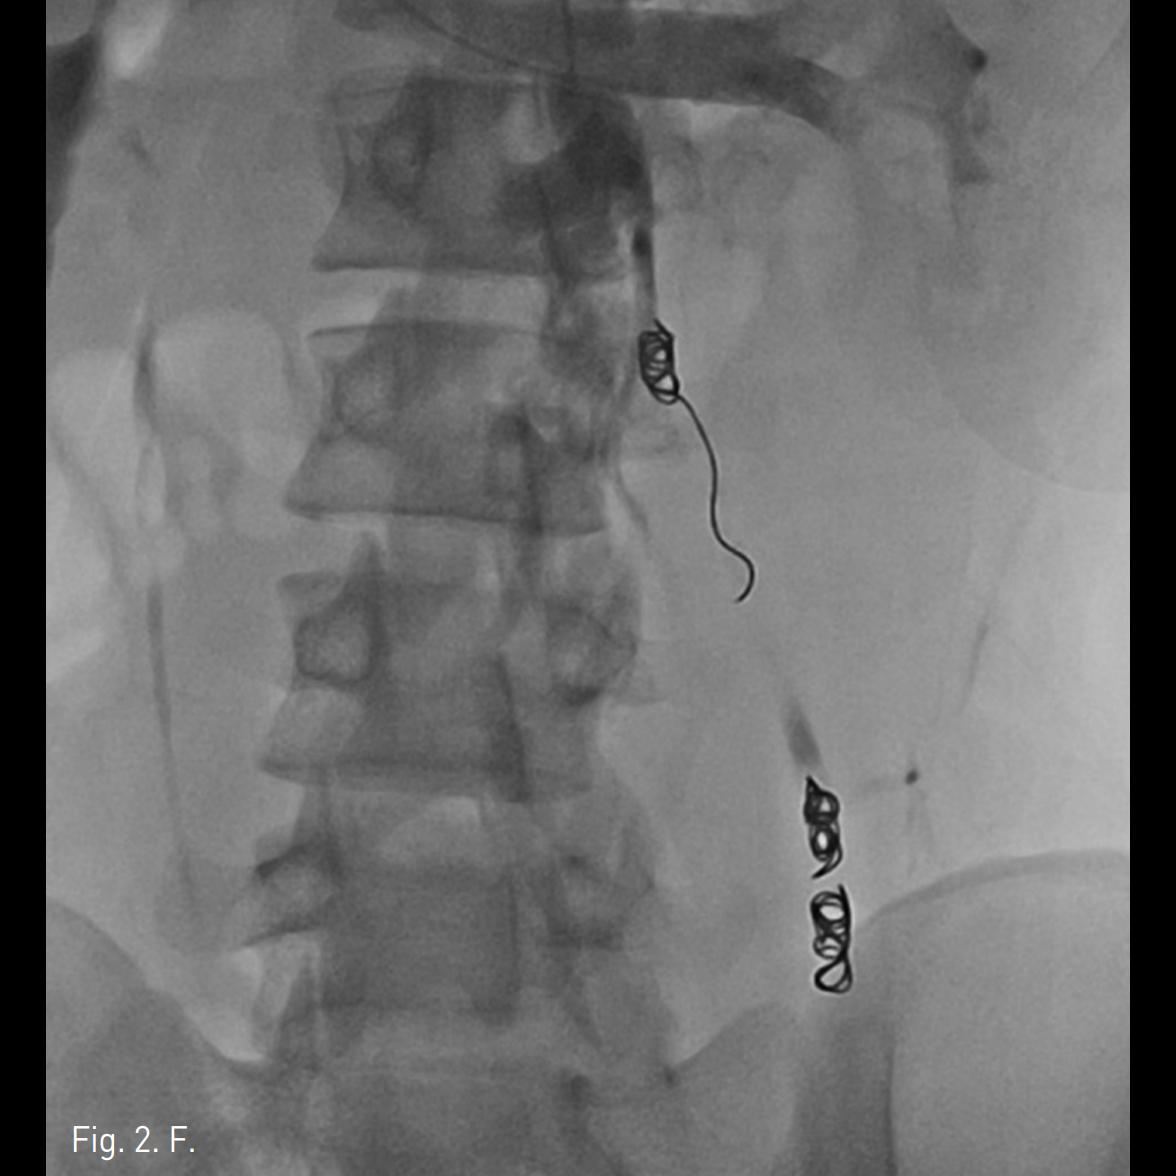

우측 상박을 tourniquet으로 묶은 후 초음파 유도 하에 우측 basilic vein을 minipuncture set을 이용해 천자하여 4Fr Cobra catheter (100cm)를 좌측 신정맥에 위치시킨 후 table tilting을 하여 조영제를 넣었을 때 좌측 spermatic vein.으로의 역류가 관찰되며 L3 level에서 retroperitoneum으로 통하는 venous tributary가 있으며 main tributary는 좌측 pampiniform plexus로 역류되는 소견이 보임(Fig. 2A, 2B). Microcatheter (Renegade, Boston Scientific, Watertown, MA)를 이용하여 보다 자세한 정맥조영을 얻었을 때 inguinal canal level에서 두 개의 정맥이 관찰됨(Fig. 2C). Subinguinal level에서 3개의 microcils (2~3mm ; micronester, Cook, Bloomington, IN)를 이용하여 색전술을 시행하였음 (Fig. 2D). 이어서 환자의 왼쪽 손가락을 이용해 inguinal level을 압박하게 하고 조영제를 주입했을 때 고환으로의 조영제 흐름이 차단된 것을 확인한 후(Fig. 2E), foam sclerotherapy (2mL of 3% STS [sodium tetradecyl sulfate, Thrombojet] + 3mL of air) 5mL를 Cobra catheter를 통해 시행함. 근위부 spermatic vein에 3개의 coils (6mm Nester coils)로 색전술을 시행함. 최종 좌측 신정맥조영술에서 spermatic vein이 조영되지 않음(Fig. 2F).

Fig. 2

F. Completion left renal venogram after sclerotherapy and coil embolization for the proximal part of the left spermatic vein shows no reflux of the contrast into the spermatic vein.